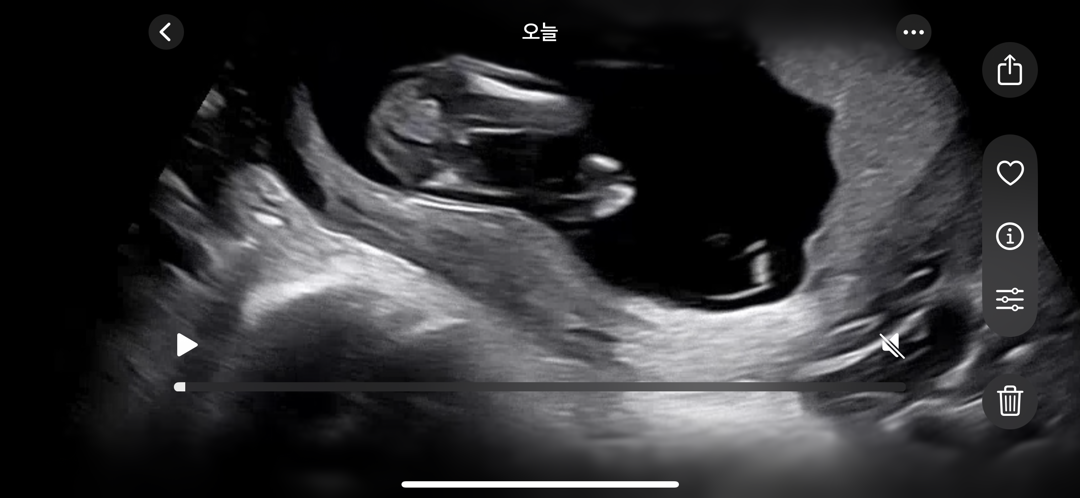

14주 2일차 각도법 봐주세요!

12주차땐 아들, 14주 2일차 오늘은 병원에선 공주님 같다고 하셨는데 뭔가 보이는 것 같아서,,, 탯줄일까요??? 공주인지 왕자인지 봐주세요~